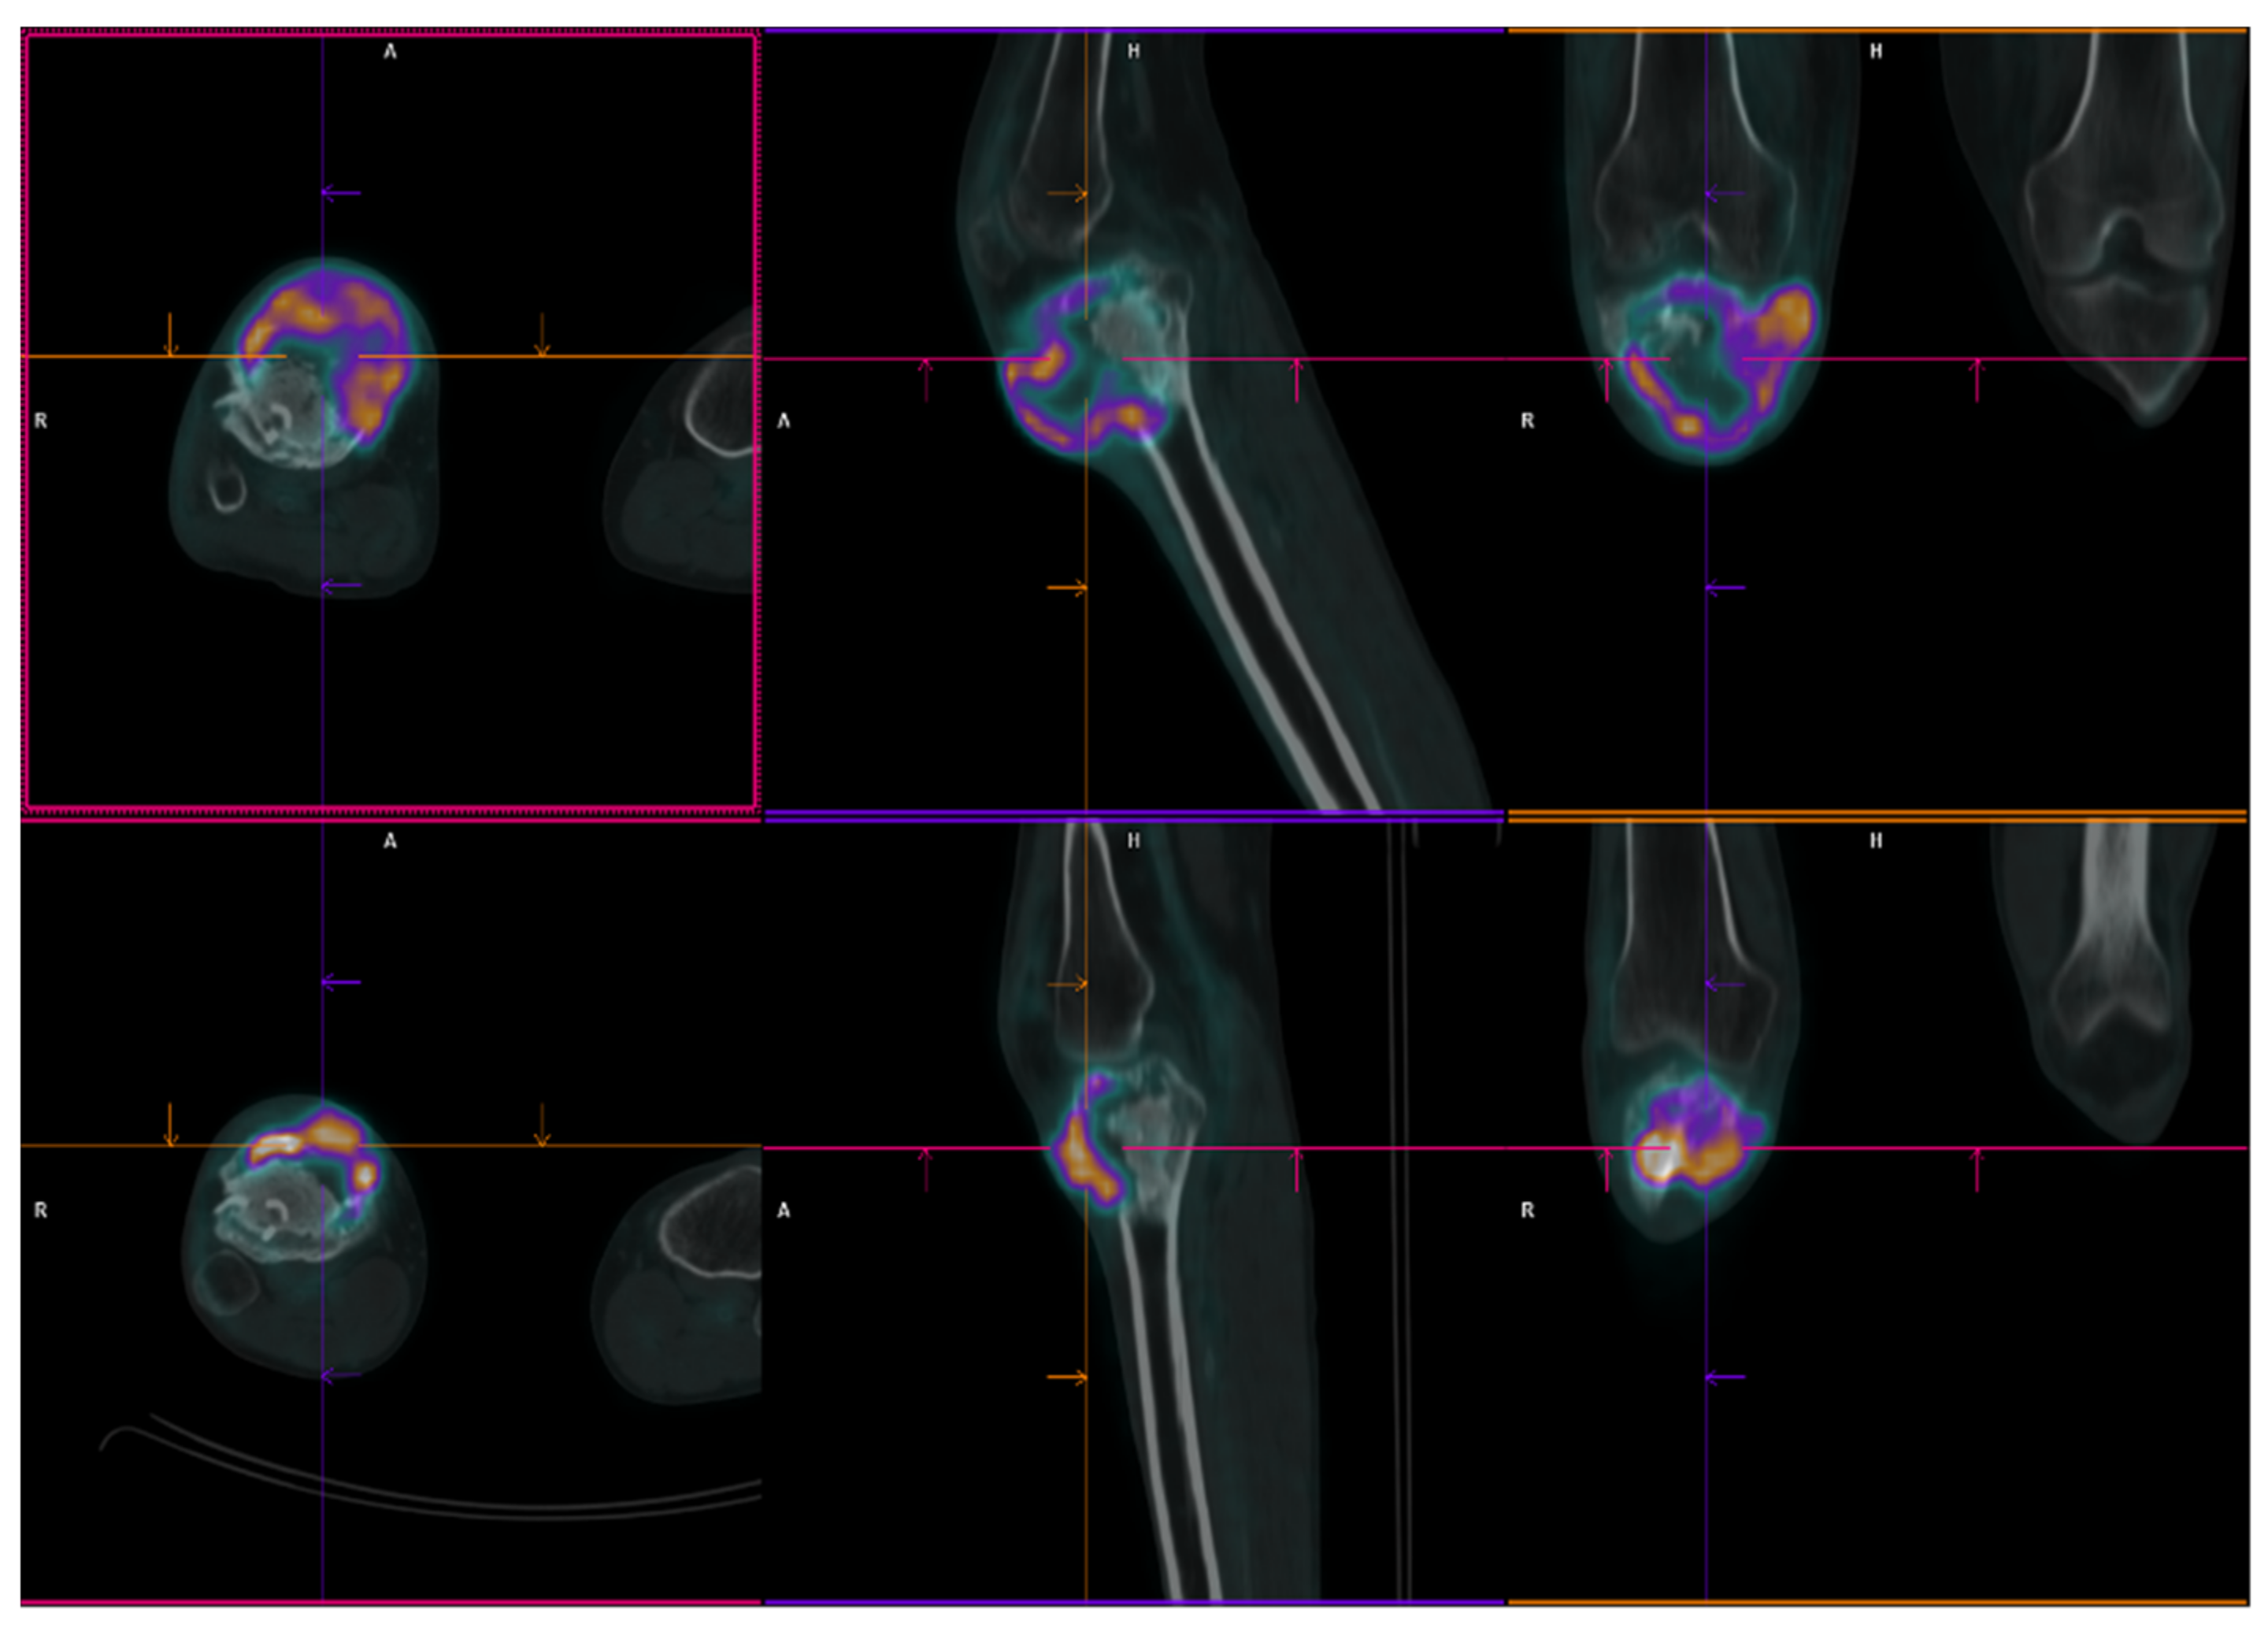

2.1. Patient 1

2.2. Patient 2

2.3. Patient 3

| Pt 1 | 29 | F | 0 | 17 July | Right femur | Curettage and bone grafts | 18 February | Neoadj denosumab (7 cycles) | 18 July Extraarticular resection: high-grade fibroblastic osteosarcoma | ISG/OS-2 | PD | I: IFO II: GEM.TXT III: PAZO | D 22 January | 9 | 53 | 43 |

| Pt 2 | 48 | M | 0 | 16 November | Right tibia | Curettage and bone grafts | 20 October | Neoadj denosumab (6 cycles) | 21 February Extraarticular resection: malignant transformation of GCTB | EURO BOSS | NED | - | FU 21 December | 51 | 64 | 13 |

| Pt 3 | 20 | F | 0 | 10 September | Left femur | Resection of the femoral head, curettage and bone grafts | 11 March | Biopsy | 11 June Biopsy: high-grade osteosarcoma G3 with aberrant expression of beta-HCG | ISG/OS-1 | PD | - | D 11 November | 9 | 14 | 5 |